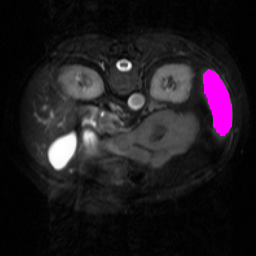

Support

Label

Proposed

In order to assess the performance of the proposed method, we compare the performance of the proposed model with excellent models in recent years. Table 1 and Table 2 shows the comparison results of different models in setting1, while Table 3 and Table 4 shows the comparison results of different models in setting2 on the data set in recent years. PANet[25] is the most widely influential few-shot model in the field of few-shot image segmentation on natural images. SENet [18] is the first few-shot segmentation model proposed for medical images. SSL-ALPNet[19] introduced the milestone of using superpixel self-supervision to train few-shot medical image models. RPNet[29] is a supervised method with a recursive mask optimization module to iteratively optimize the segmentation mask, [27] adapt it into the same self-supervision learning framework and applies setting1 to it and denoted as SSL-RPNet; CRAPNet[27] is the latest SOTA model for 2023. Compared with CRAPNet, our method outperforms most of the state-of-the-art models and only slightly outperforms CRAPNet. Figures 3 and 4 show examples of the model’s segmentation predictions on different datasets, respectively; The first row is the support map, the second row is the label map, and the third row is the segmentation prediction of the model.